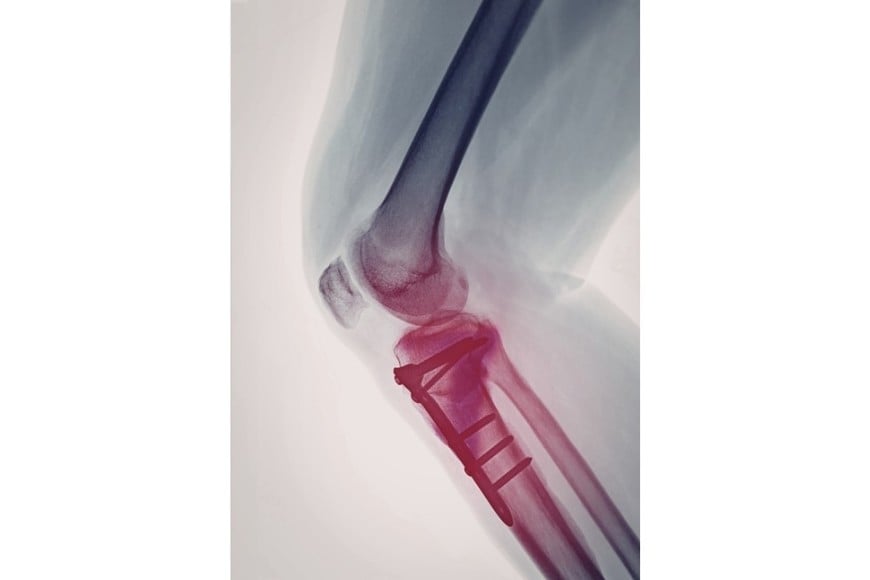

El procedimiento, realizado a fines de 2025, puso al descubierto un escenario preocupante: la presencia de un tornillo quirúrgico falsificado y otros implantes de origen desconocido, sin respaldo documental ni registro sanitario. La medida quedó formalizada en la Disposición 2223/2026, publicada en el Boletin Oficial, y tiene alcance en todo el territorio nacional.

El caso más relevante fue el de un tornillo de interferencia para ligamento cruzado, rotulado como perteneciente a la marca Stryker. Tras un análisis detallado, se determinó que se trataba de una falsificación.

Las diferencias con el producto original fueron contundentes. Mientras el implante legítimo presenta un color gris opaco, el detectado era incoloro y translúcido, lo que sugiere una composición distinta. Además, el empaque no coincidía con los estándares del fabricante: estaba contenido en una bolsa tipo pouch de una marca que no es utilizada por la empresa original.

Otro punto clave fue el método de esterilización. El producto auténtico se esteriliza mediante radiación gamma, mientras que el hallado indicaba haber sido preparado para esterilización por vapor o formaldehído, un procedimiento incompatible con ese tipo de dispositivo.

En el caso del tornillo falsificado, la incertidumbre sobre su composición y resistencia mecánica abre la posibilidad de fallas estructurales una vez implantado. En cirugías como las de ligamento cruzado, este tipo de dispositivos cumple una función clave en la estabilidad de la articulación.